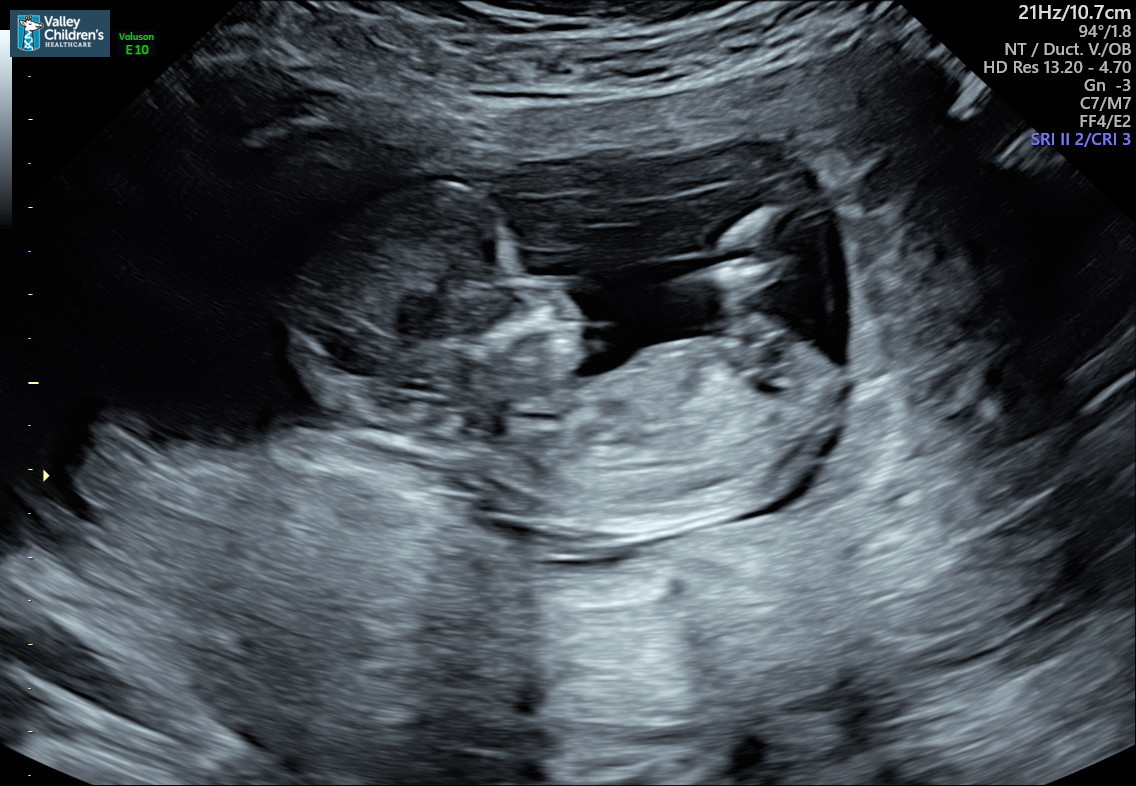

Hello all me and my wife are pregnant with our second and we’re on the fence and can’t tell if a boy or girl?? Any help would be appreciated these pictures will be from 12W 4D, thanks in advance:)Attachment 41451Attachment 41452